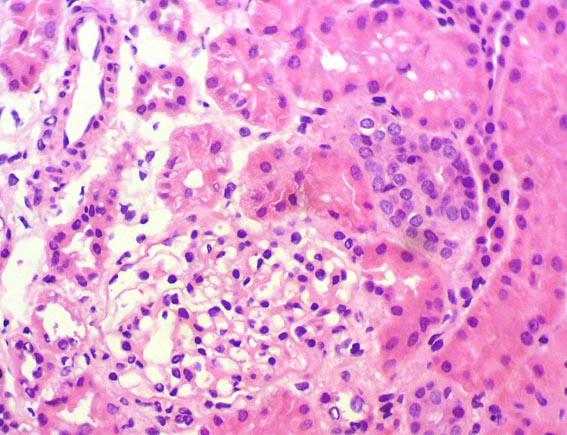

The patient is a 4-year-old girl who presented nephrotic syndrome in the first year of life, with biopsy in which focal segmental glomerulosclerosis was diagnosed. There was no response to multiple treatments. Molecular studies were unable to detect a specific genetic alteration. He developed ESRD at 3 years of age. She was in hemodialysis few months and was transplanted from a dead donor. Nephrectomy of a native kidney was done. Before the transplant, on dialysis, she had low urine output and non-nephrotic proteinuria without hypoalbuminemia or dyslipidemia. After transplantation presented progressive increase in proteinuria. Four post-transplant weeks there was complete nephrotic syndrome with proteinuria >100 mg/m2/h, dyslipidemia and hypoalbuminemia. Serum creatinine 0.5 mg/dL.

A renal biopsy was done, see the images.

Figure 3. H&E, X400.